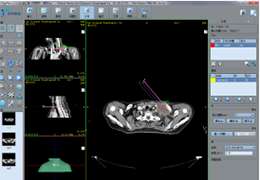

Talairach Tools

Talairach transformation is performed in two steps. The first step consists of rotating the 3D data set for each subject to be aligned with the stereotaxic axes. For this step the location of the anterior commissure (AC) and the posterior commissure (PC) as well as two rotation parameters for midsagittal alignment has to be specified interactively. In the second step the extreme points of the cerebrum are specified. These points together with the AC and PC coordinates are then used to scale the 3D data sets into the dimensions of the standard brain of the Talairach and Tournaux atlas.